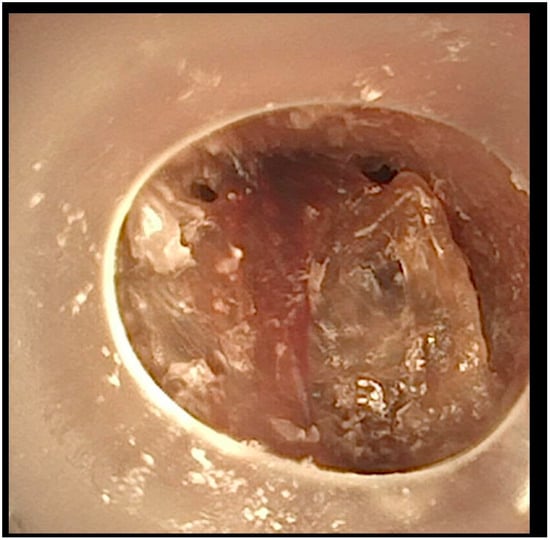

A flexible bronchoscopic examination at our facility showed extensive granulomatous tissue distal to the tracheostomy tube, with significant inflammation in the distal trachea and bronchi (Figure 2).

To address the recurrent tracheal obstruction and granulomatous tissue, we implemented a management approach. This involved shortening the tracheostomy tube and changing the size of the tube every two weeks to prevent further granulation tissue formation. Additionally, we conducted flexible bronchoscopic examinations every 8 weeks over a 6-month period to monitor the healing process and ensure proper airway patency.

After this comprehensive approach, the patient’s tracheal obstruction episodes resolved, and the granulomatous tissue showed significant regression (Figure 3).

Figure 2. Tracheoscopic visualization at the distal end of the tracheostomy cannula. The cannula abrades the granuloma.

Figure 3. Image taken after 3 months of specific cannula management.